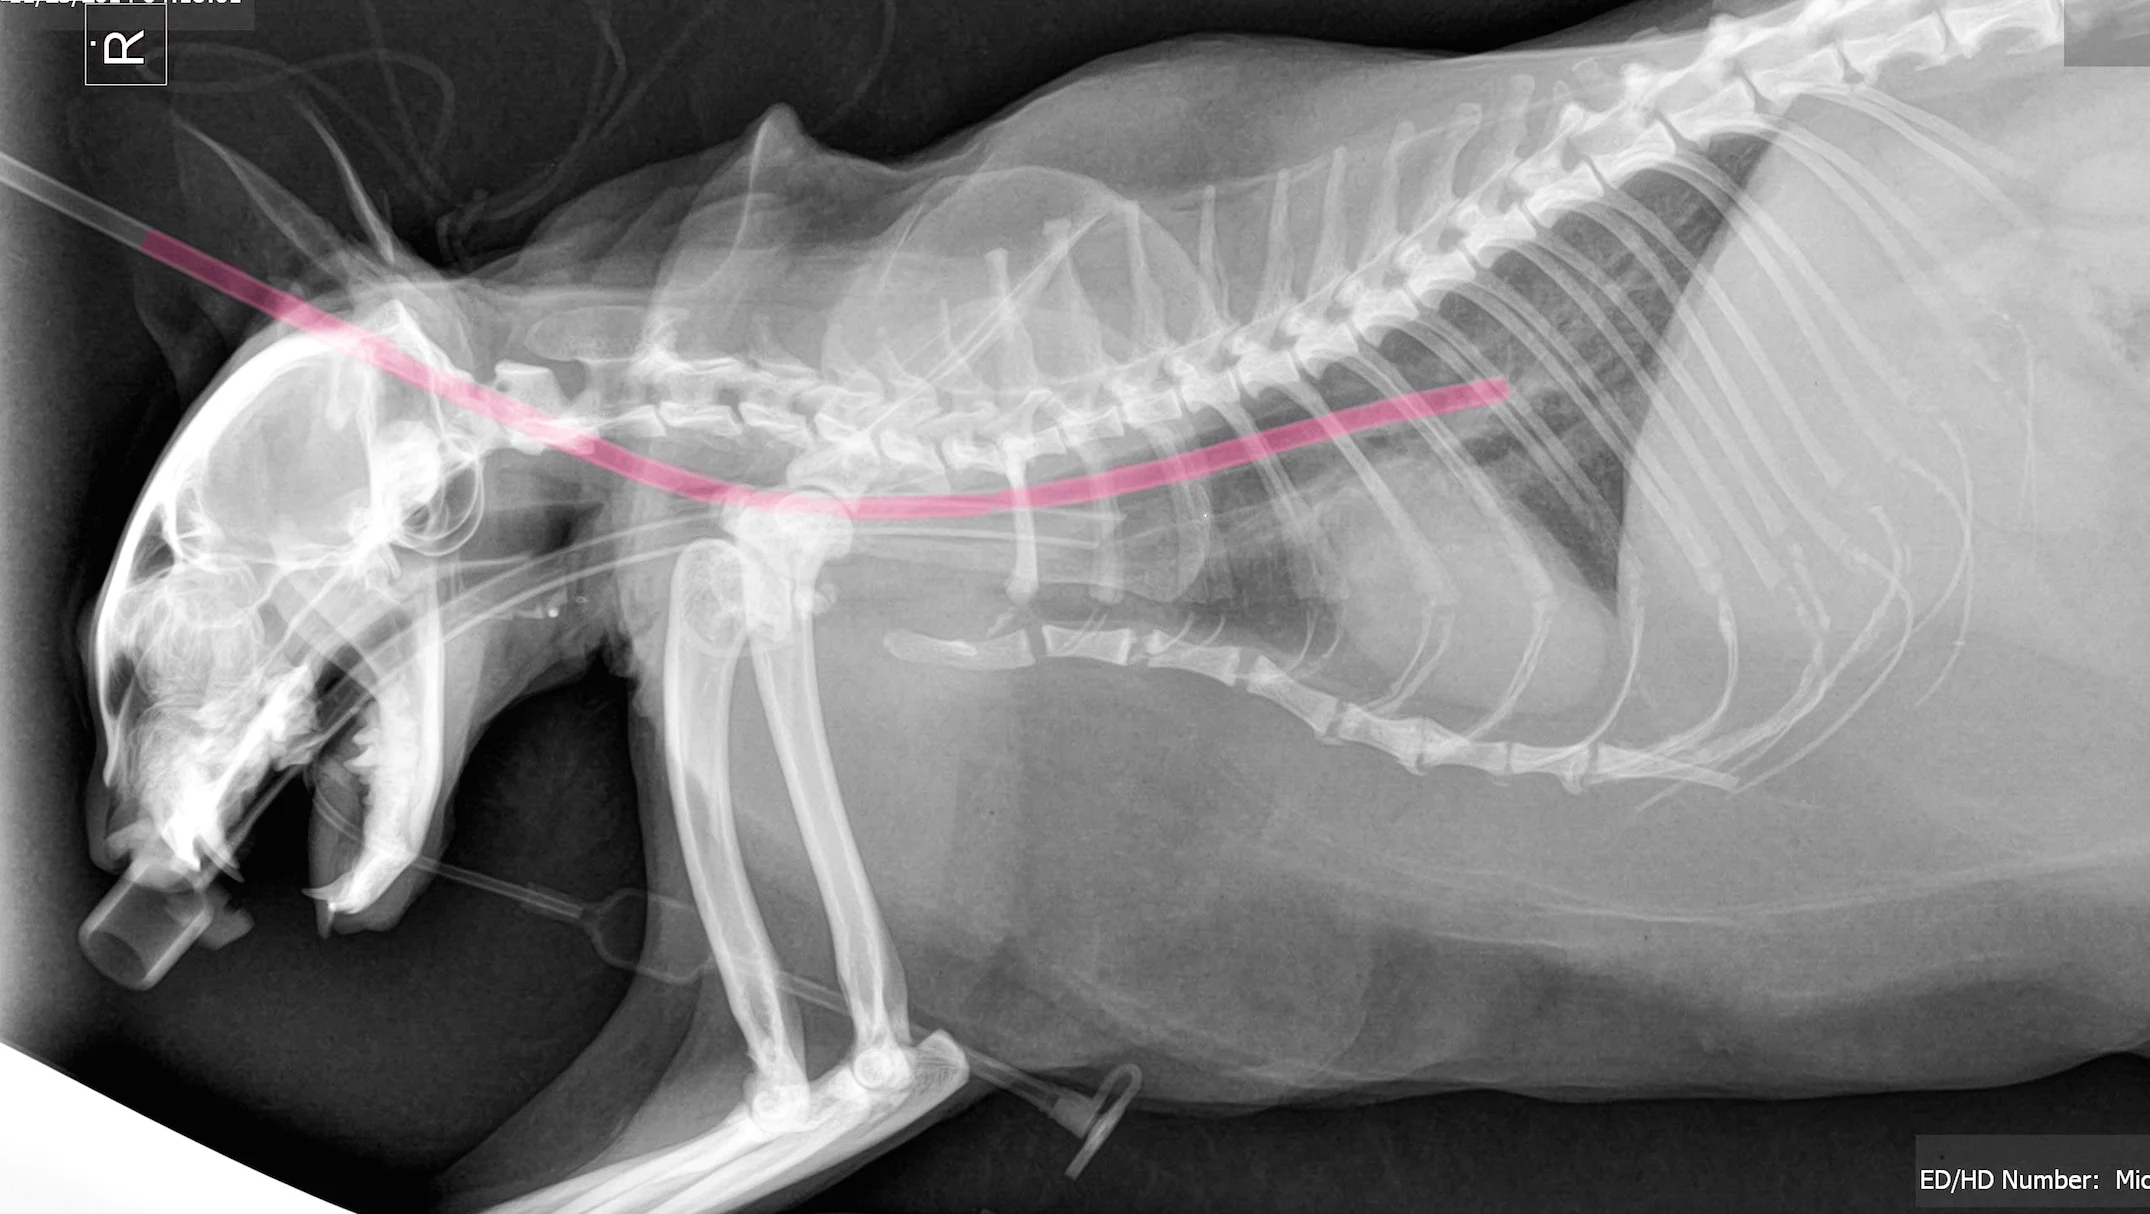

How To Place An Esophagostomy Tube Vetgirl Veterinary Ce Podcasts

Feeding Tubes For Dogs And Cats Veterinary Partner Vin

Feeding Tubes For Cats